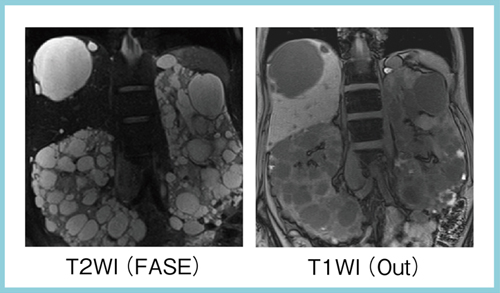

図6は,膵尾部の膵管内乳頭粘液性腫瘍(IPMN)の経過観察画像で,1.5Tおよび直近の3TのMRCPで,肝内胆管が明瞭に描出されている。図7は,水を含んだ画像の評価のために撮像した常染色体優性多発性嚢胞腎(ADPKD)の経過観察画像で,肝臓や両側の腎臓に多数の嚢胞があるが,水の多い病変でも均一な腹部画像が得られている。

図7 常染色体優性多発性嚢胞腎(ADPKD)経過観察